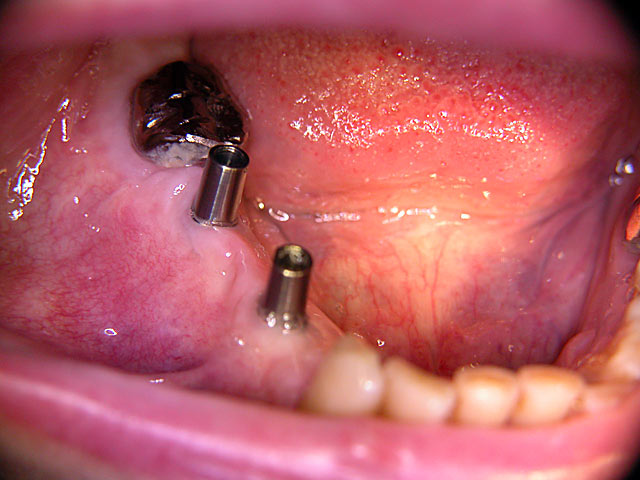

Die folgenden Patientenfälle sollen Ihnen einen Einblick in die Möglichkeiten der modernen Implantation geben.

Kugelkopf-Implantation: